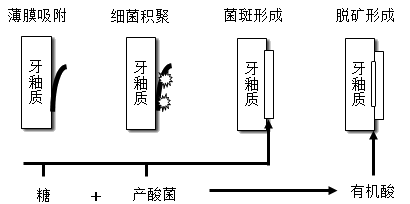

获得性膜形成和细菌初期聚集—细菌迅速生长繁殖—菌斑成熟